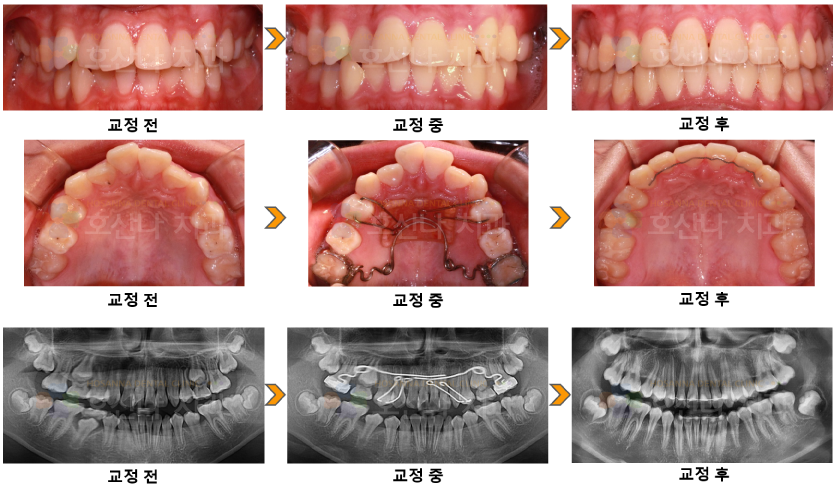

교정펜듈럼 교정 시술 증례

< 펜듈럼 교정 시술 증례 >

1. 치료대상

male / 11y 9m

2. 교정치료이유

덧니가 있어요 / 앞니가 튀어나왔어요

3. 진단결과

1) Skeletal CL II

2) U crowding / protrusion  U 1

3) L ant moderate crowding

4) Large OJ

5) Class II canine, molarrelation

4. Dr.Koo Memo

위 아래 앞니가 닿지 않아 발음이나 식사 시에 불편하고 심미적으로도 개선을 하기 위해 내원하셨습니다.

상악전치는 상당한 돌출이 있지만 안모는 양호 하여 발치 없이 펜듈럼으로 교정을 진행하였습니다.

펜듈럼 사용기간은 6개월 정도 되었고 교정 결과 입술과 안모가 자연스러우면서 심한 OJ 개선과 배

열 그리고 기능적 교합이 형성되었습니다.

5.교정기간

1y 11m